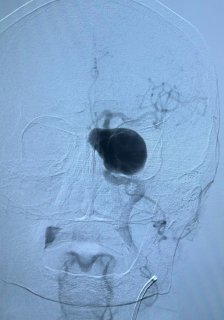

Врачи на основании снимков МРТ и селективной церебральной ангиографии выявили у пациента множественные аневризмы головного мозга, инцидентальную гигантскую фузиформную аневризму кавернозно-параклиноидного сегмента левой внутренней сонной артерии, размерами 50,3*48,2 мм., инцидентальную фузиформную аневризму параклиноидного сегмента правой внутренней сонной артерии, размерами 16,5*14,5 мм.

Учитывая наличие гигантской аневризмы, клинический и неврологический статус пациента, а также был крайне высокий риск разрыва аневризмы и окклюзии сосуда при эмболизации аневризмы, врачами было принято решение о проведении операции в 2 этапа. После операции пациент чувствует себя хорошо.